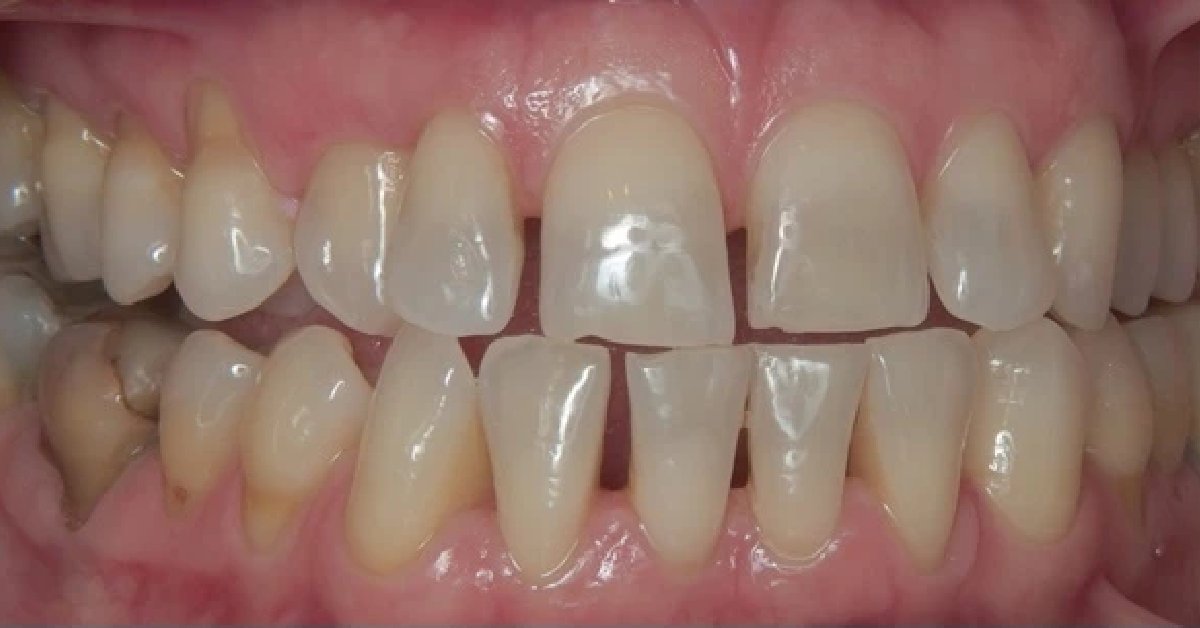

Vårt arbeid

Alle pasienter som vises har gitt skriftlig samtykke til at bildene kan brukes på klinikkens nettside.

Ønsker du en vurdering av behov for tannregulering, kan du ta kontakt med klinikken for time til konsultasjon.